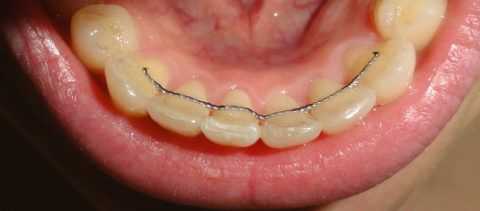

В дошкольном возрасте, когда челюсти ребенка находятся в процессе роста, для коррекции мезиального прикуса назначается миофункциональная гимнастика и массаж альвеолярного отростка верхней челюсти; при необходимости проводится пластика уздечки языка. Для отучения ребенка от вредных оральных привычек рекомендуется использование вестибулярных пластинок. Ортодонтическое лечение на данном этапе по показаниям может проводиться с помощью аппарата Брюкля, каппы Бынина. Существует мнение, что наилучшие результаты лечения мезиального прикуса в период молочного и раннего сменного прикуса достигаются в случае использования лицевой маски.

В период сменного прикуса лечение мезиальной окклюзии проводится с использованием активаторов Андрезена-Гойпля, Кламмта, Френкеля, аппаратов Вундерера или Персина. С установлением постоянного прикуса для коррекции аномальной окклюзии применяется несъемная ортодонтическая техника - брекет-системы. Одновременно с ортодонтическим этапом проводятся логопедические занятия по коррекции дислалии.